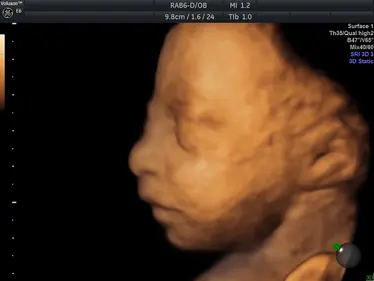

Gallery: 4D Scan Images & Videos

All of the baby scans we perform here at First Encounters are carried out using top-quality ultrasound equipment. For 3D/4D scans, we use the GE Voluson E6, featuring genuine HDLive technology. GE Healthcare are the world’s leading providers of pregnancy scanning equipment, and HD Live scans give an unparalleled level of detail and clarity.

Scroll down to view some examples of the 4D scan images and videos our sonographers are able to capture.

4D Scan Images

During your 3D/4D scan, we’ll capture multiple photographs of your unborn baby, giving you and your family a set of stunning keepsakes that you’ll treasure forever. All of your scan images will be available to download from photocloud™, plus we can provide glossy souvenir photos for you to take home.